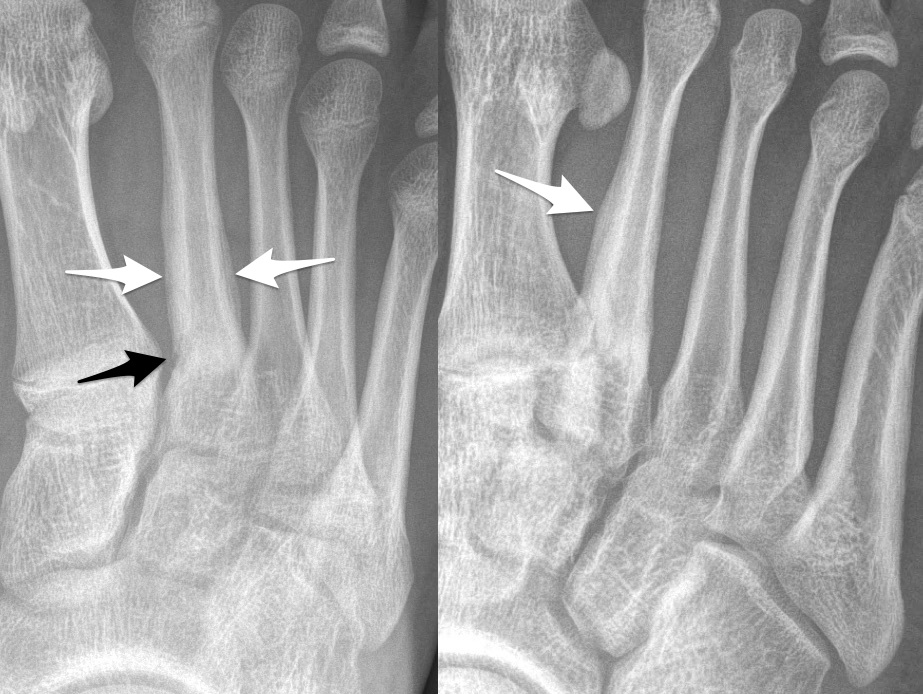

Gãy xương mệt mỏi

» Thông tin: Nữ giới – 23 tuổi.

» Lâm sàng: Đau bàn chân.

Gãy xương bàn III

# Gãy xương bàn II

# Gãy xương bàn III

# Gãy xương mệt mỏi xương bàn V bàn chân.